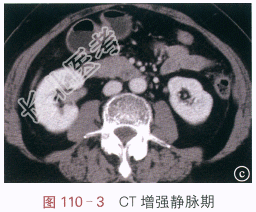

读片分析:图110-1IVP示右侧肾下盏及肾盂内有充盈缺损影,边缘欠规则;图110-2(动脉期)与图110-3(静脉期)示CT增强扫描后肾盂内病灶有强化,CT值分别约为91.3Hu和102.1Hu,平扫时(未提供)病灶CT约为30.6Hu;图110-4CTU示肾盂内充盈缺损。结合病史,可知患者为肾盂癌。